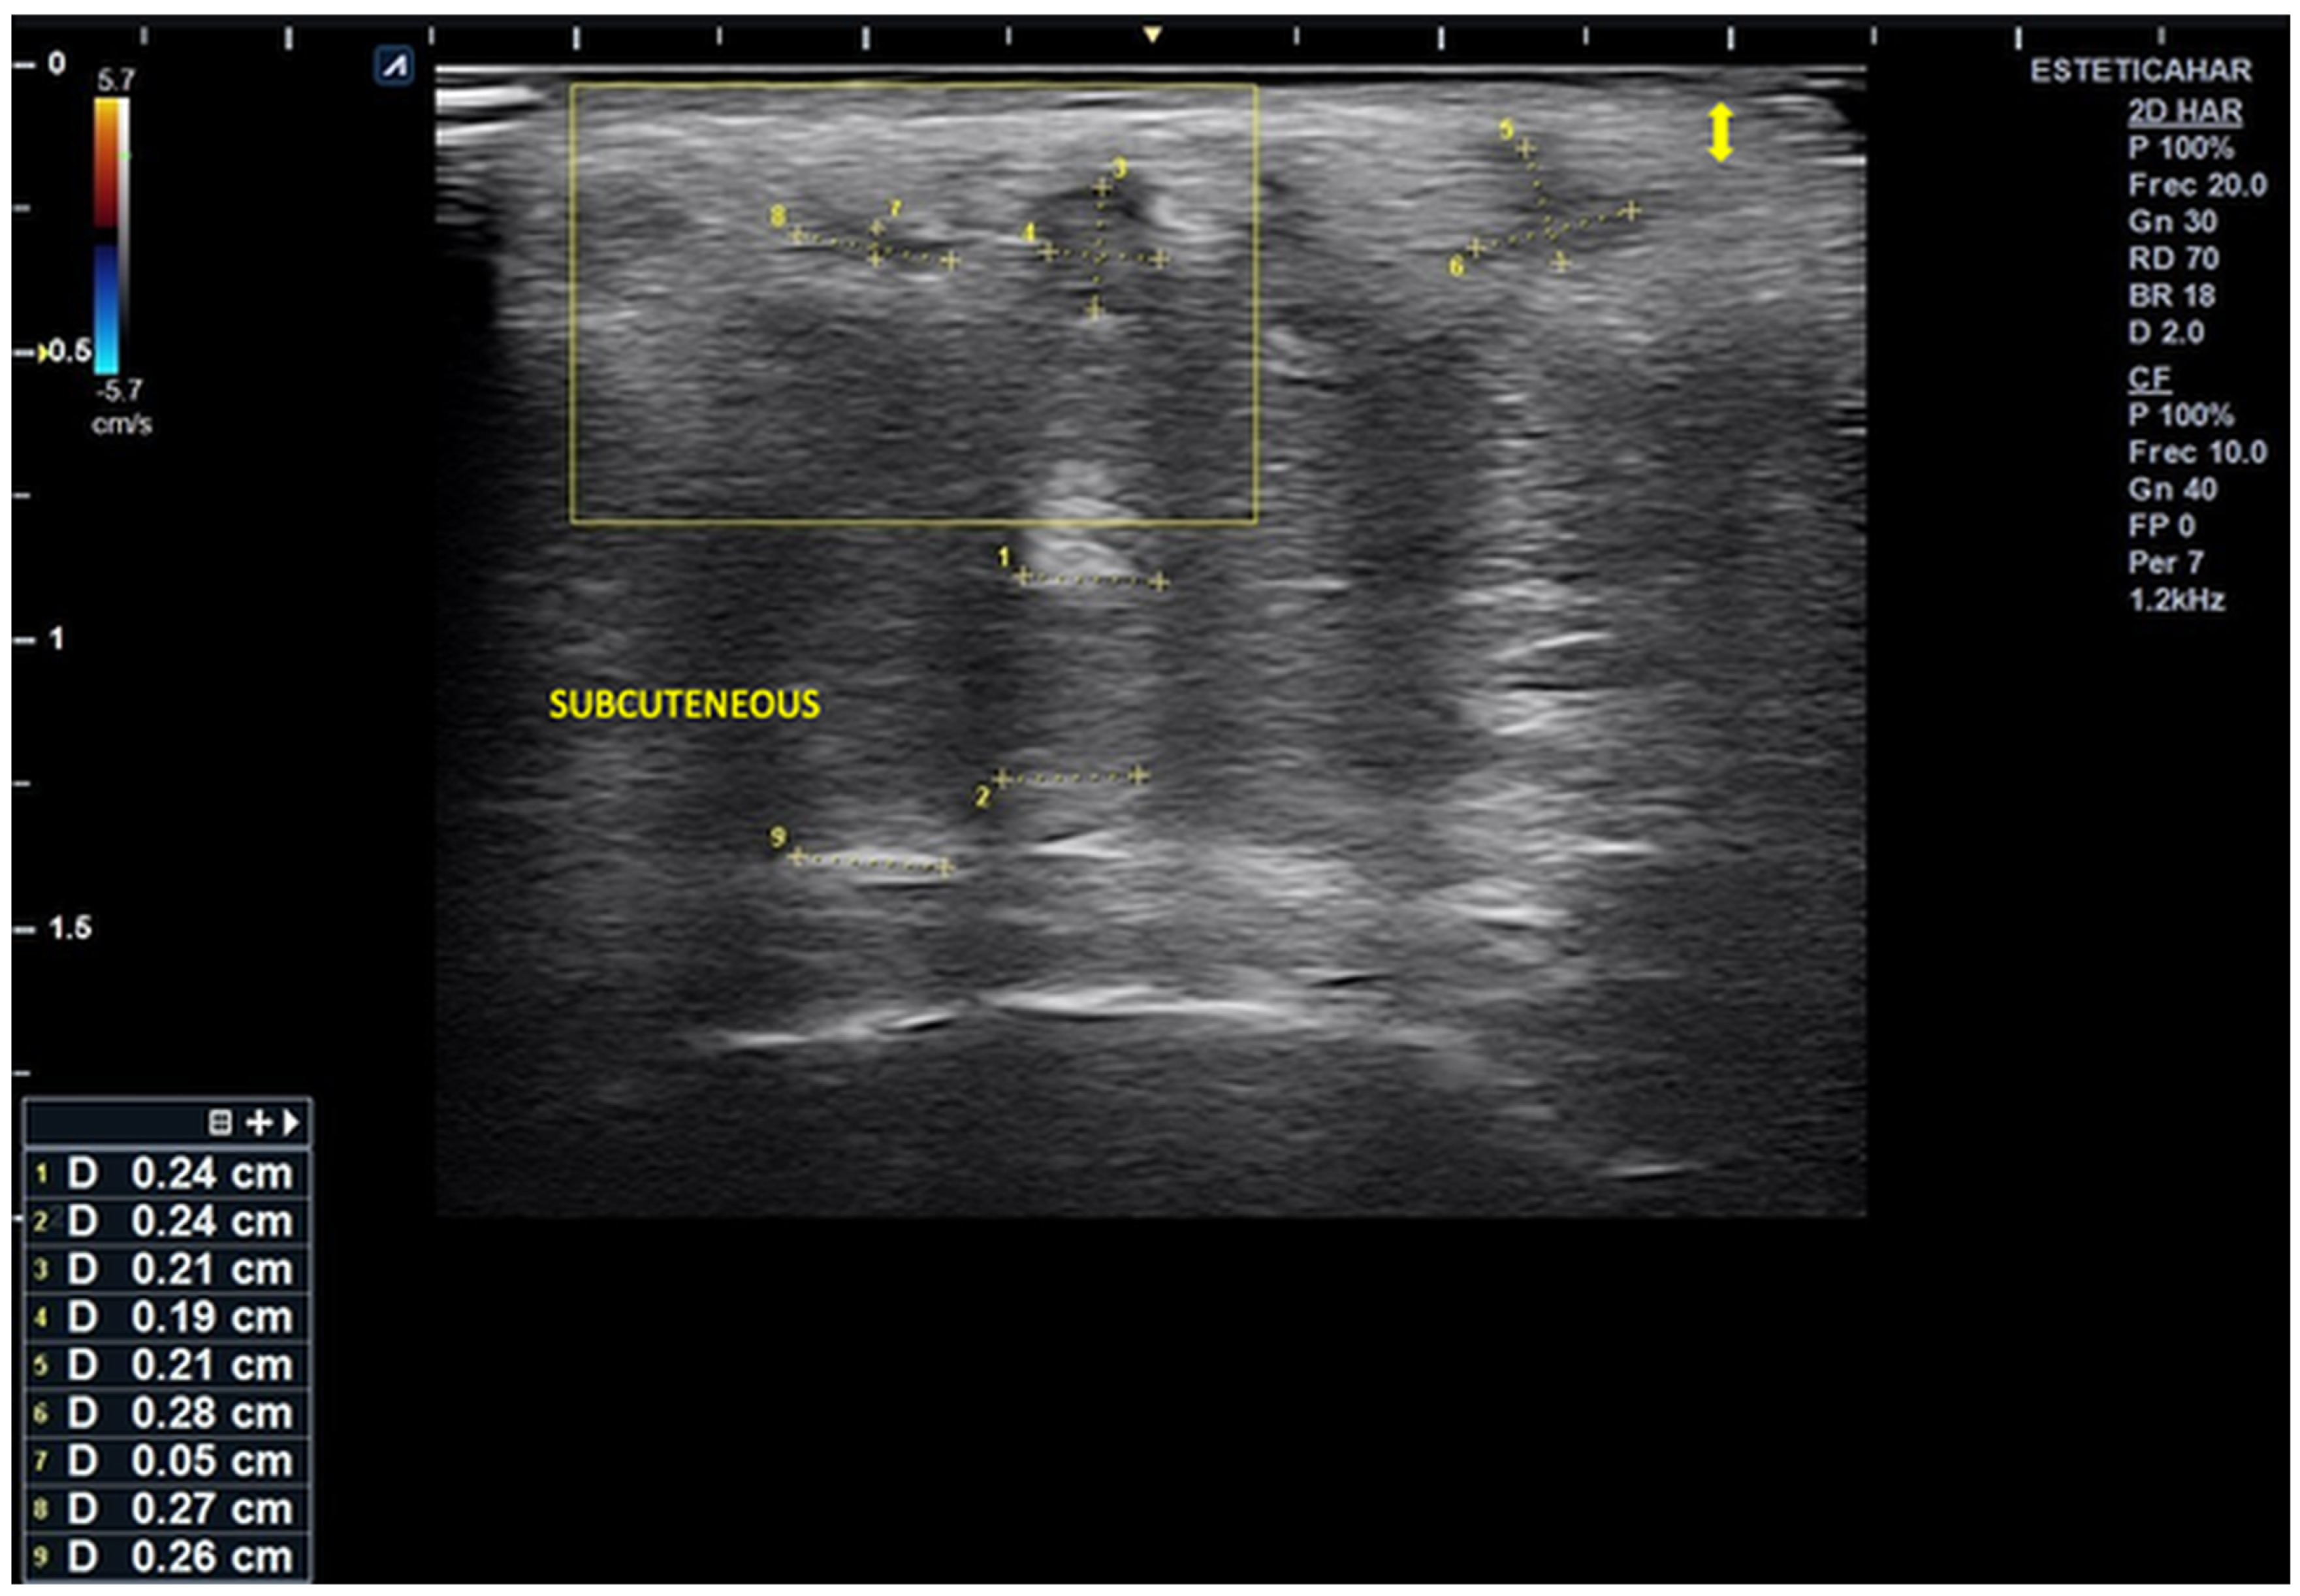

High-resolution cutaneous ultrasound demonstrated homogeneous hypoechoic images compatible with well-demarcated subcutaneous inflammatory infiltrates, with no evidence of fluid collections or necrosis.

Ultrasound imaging revealed alternating columnar hypoechoic areas and distributed linear hyperechoic zones. There were disruptions in the normal echoanatomy, as evidenced by diffuse hypoechogenicity starting at the basal dermis, which obscured the distinction of deeper anatomical planes and was associated with a slight increase in microvascularization.

In the right lateral submalar area, poor visualization of the soft tissue echoanatomy was noted, with uniform isoechogenicity extending from the posterior dermis to the bone interface. This finding is likely related to infiltration by dermal filler material that was poorly integrated into the surrounding tissue (Figure 2 and Figure 3).

Notably, there is a markedly thickened subepidermal low-echogenicity band (SLEB), which is likely indicative of obstructive lymphedema.

Figure 2. Ultrasound image of the right lateral malar region demonstrating destructured epidermis and dermis (Reports 08 00194 i001). The scan reveals alternating hyper- and hypoechoic columnar areas extending from the posterior dermis to the bone plane, which hinder clear differentiation of tissue layers based on echogenicity. The largest area, measuring 0.24 cm in width, is most likely associated with deposits of hybrid material (hyperdiluted collagen stimulator). Additionally, three smaller, rounded hypoechoic deposits are observed in the more superficial subcutaneous region. The largest of these measures 0.27 × 0.26 cm and is likely associated with poor integration of the injected material, without evidence of increased microvascularization.